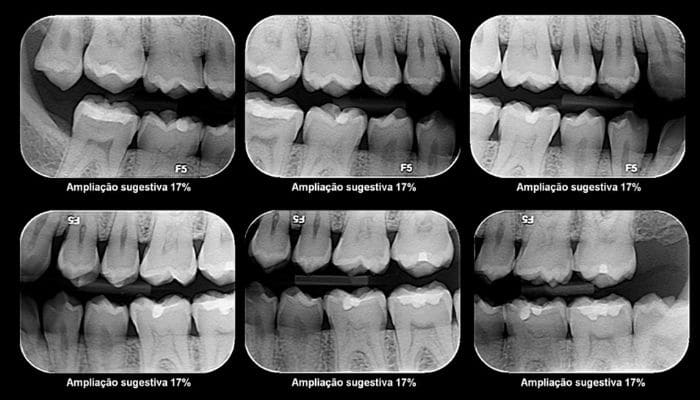

A periodontite aparece com o acumulo da placa bacteriana nos dentes, ela produz toxinas que incomodam a gengiva, gerando uma inflamação.

E essa inflamação, se não for tratada, pode evoluir para uma gengivite. E a evolução da gengivite é justamente a periodontite.

Ou seja, a inflamação se dissemina para o osso e tecidos de suporte dos dentes, deixando-os moles a ponto de precisarem ser extraídos.